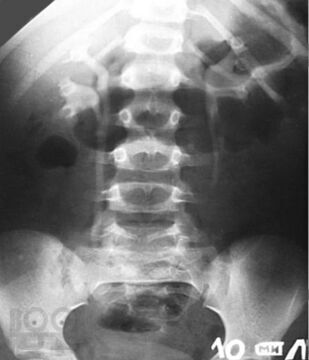

Пороки развития мочеполовой системы

Учебное пособие «Пороки развития мочеполовой системы» составлено в соответствии с программой по дисциплине «Патологическая анатомия, клиническая патологическая анатомия» для студентов по специальностям «Лечебное дело», «Педиатрия», «Медико-профилактическое дело». Учебное пособие может быть использовано во время практических занятий студентами лечебного, педиатрического и медико-профилактического факультетов.